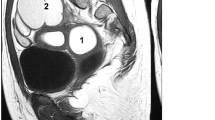

We identified TBC1D1 variants in two unrelated patients, Fc-M-1 and Fc-M-3 (Table 2). Fc-M-1 was diagnosed as type II MRKH syndrome (European Society of Human Reproduction and Embryology [ESHRE] classification: U5bC4V4) with full uterine agenesis, left pelvic kidney dysfunction, congenital anal atresia with vestibular fistula, ventricular septal defect, and accessory auricle (Table 1, Fig. 1A–C). Fc-M-3 was diagnosed as type I MRKH syndrome (ESHRE classification: U5bC4V4) with uterine remnants without a rudimentary cavity (Table 1 and Fig. 1D).

TBC1D1 mutation in patients with MRKH. A Image of patient Fc-M-1 with a diagnosis of MRKH. No uterine echo was evident in the pelvic ultrasound (indicated by *) behind the bladder (denoted by B). B Image of patient Fc-M-1 with a diagnosis of MRKH. The right renal (R–R) region is enlarged. C Image of patient Fc-M-1 with a diagnosis of MRKH. The left renal (L–R) region was dysplastic and located in the left lower abdomen (pelvic ectopic kidney). The region was 4.0 cm in length. A cystic cavity measuring 1.8 * 1.6 cm was evident. The renogram showed that the left kidney had no function. D Pelvic ultrasound image of patient Fc-M-3 with a diagnosis of MRKH. B denotes bladder and U denotes aplastic uterus without rudimentary cavity. E TBC1D1 is highly expressed in the human uterus. The data were obtained from an online database (https://varsome.com/gene/TBC1D1). The red arrow denotes the expression level of TBC1D1 in the human uterus. F Sanger sequencing confirmation of the heterozygous TBC1D1 variant in patient Fc-M-1. The patient’s father (I-1) also carried the same heterozygous variant. The patient’s mother (I-2) harbored two wild-type (WT) alleles. The red arrow indicates the variant site (c.2553delC); MT, mutated allele. G The domain and mutation in TBC1D1. Full-length TBC1D1 is 1168 amino acids (aa), and includes the PID domain from aa 246 to 404 (blue box) and the catalytic Rab-GAP TBC domain from aa 800 to 994 (red box). The p.R854Efs*24 mutation results in a predicted 23-aa frameshift sequence in the protein resulting in a nonsense mutation; WT, wild type allele. (H) Sanger sequencing validating the TBC1D1 variant in patient Fc-M-3. The red arrow indicates the variant site (c.1069G>C). I The wild-type (green) and p.E357Q mutant protein (red) structure for amino acids at positions 164 to 371 were predicted by RoseTTAFold. The wild-type sequence and the p.E357Q mutant sequence were aligned by VMD software

TBC1D1 was highly expressed in the uterus (Fig. 1E). Fc-M-1 harbored a frameshift c.2553delC (p.R854Efs*24) variant (Fig. 1F) inherited from her father (Fig. 1F). Therefore, TBC1D1 variant c.2553delC was associated with MRKH syndrome within this family. The c.2553delC variant of TBC1D1 was predicted to produce a truncated p.R854Efs*24 protein, which would destroy the Rab-GAP TBC domain of the TBC1D1 protein and lead to the loss of C-terminal sequences (Fig. 1G). The c.2553delC variant was absent in the gnomAD East Asian population. It was classified as a pathogenic variant (PVS1 + PM2 + PP3) according to ACMG guidelines.

TBC1D1

TBC1D1 encodes a Rab-GTPase-activating protein and is involved in regulating the trafficking of GLUT4 storage vesicles to the cell surface [19]. Previous studies have found that heterozygous mutation of TBC1D1 is associated with congenital anomalies of the kidneys and urinary tract (CAKUT) [20, 21]. The TBC1D1 mutation may promote the pathogenesis of CAKUT through its role in glucose homeostasis [20]. Patient Fc-M-1 harboring the TBC1D1 truncating variant found in this study also had CAKUT; the left pelvic kidney did not function and the right kidney was enlarged as a compensatory response. Type II MRKH syndrome is usually complicated by abnormalities in the urinary system. Therefore, the study findings suggest that attention should be paid to whether patients with type II MRKH syndrome, especially those with urinary system abnormalities, carry genetic variants related to CAKUT. A previous study by our group has also shown that sequence variants related to CAKUT could be associated with another complex reproductive tract malformation, which is related to the Herlyn–Werner–Wunderlich syndrome [17].